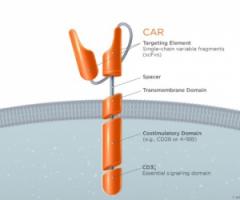

LYMPHOME: L'immunothérapie par CAR T-cells, une voie prometteuse vers la rémission